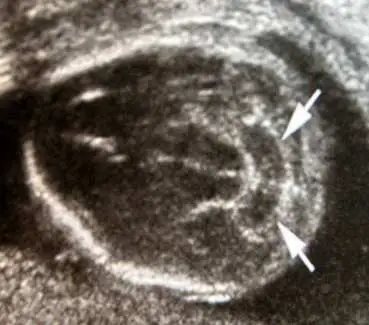

承上題【29 歲孕婦,G3P2 ,妊娠 18 週,接受超音波檢查,結果如圖所示,圖中箭頭所指之胎兒異常器官名稱與特徵( sign )為何? 】,檢查結果最可能合併的畸形為下列何者?

本題為上一題(Q53)的延伸,超音波發現 banana sign(小腦彎曲呈香蕉形),詢問最可能合併的胎兒畸形。Banana sign 是開放性神經管缺損(open neural tube defect)——特別是脊髓脊膜膨出(myelomeningocele)——所引起的 Arnold-Chiari II 型畸形之特徵表現,因此最可能合併的畸形為神經管缺損(neural tube defect, NTD),而非染色體異常。

超音波影像呈現胎兒頭部橫切面,後顱窩可見兩支白色箭頭指向小腦——小腦外形呈向前彎曲的弧形(banana shape),失去正常啞鈴形/圓形,後顱窩狹小,cisterna magna 空間消失。此為典型 banana sign,由開放性脊椎裂造成的 Arnold-Chiari II 型畸形所致。

注意:本題影像與上一題(Q53)相同,均來自同一超音波掃描,延伸詢問此超音波發現最常見的合併畸形類型。